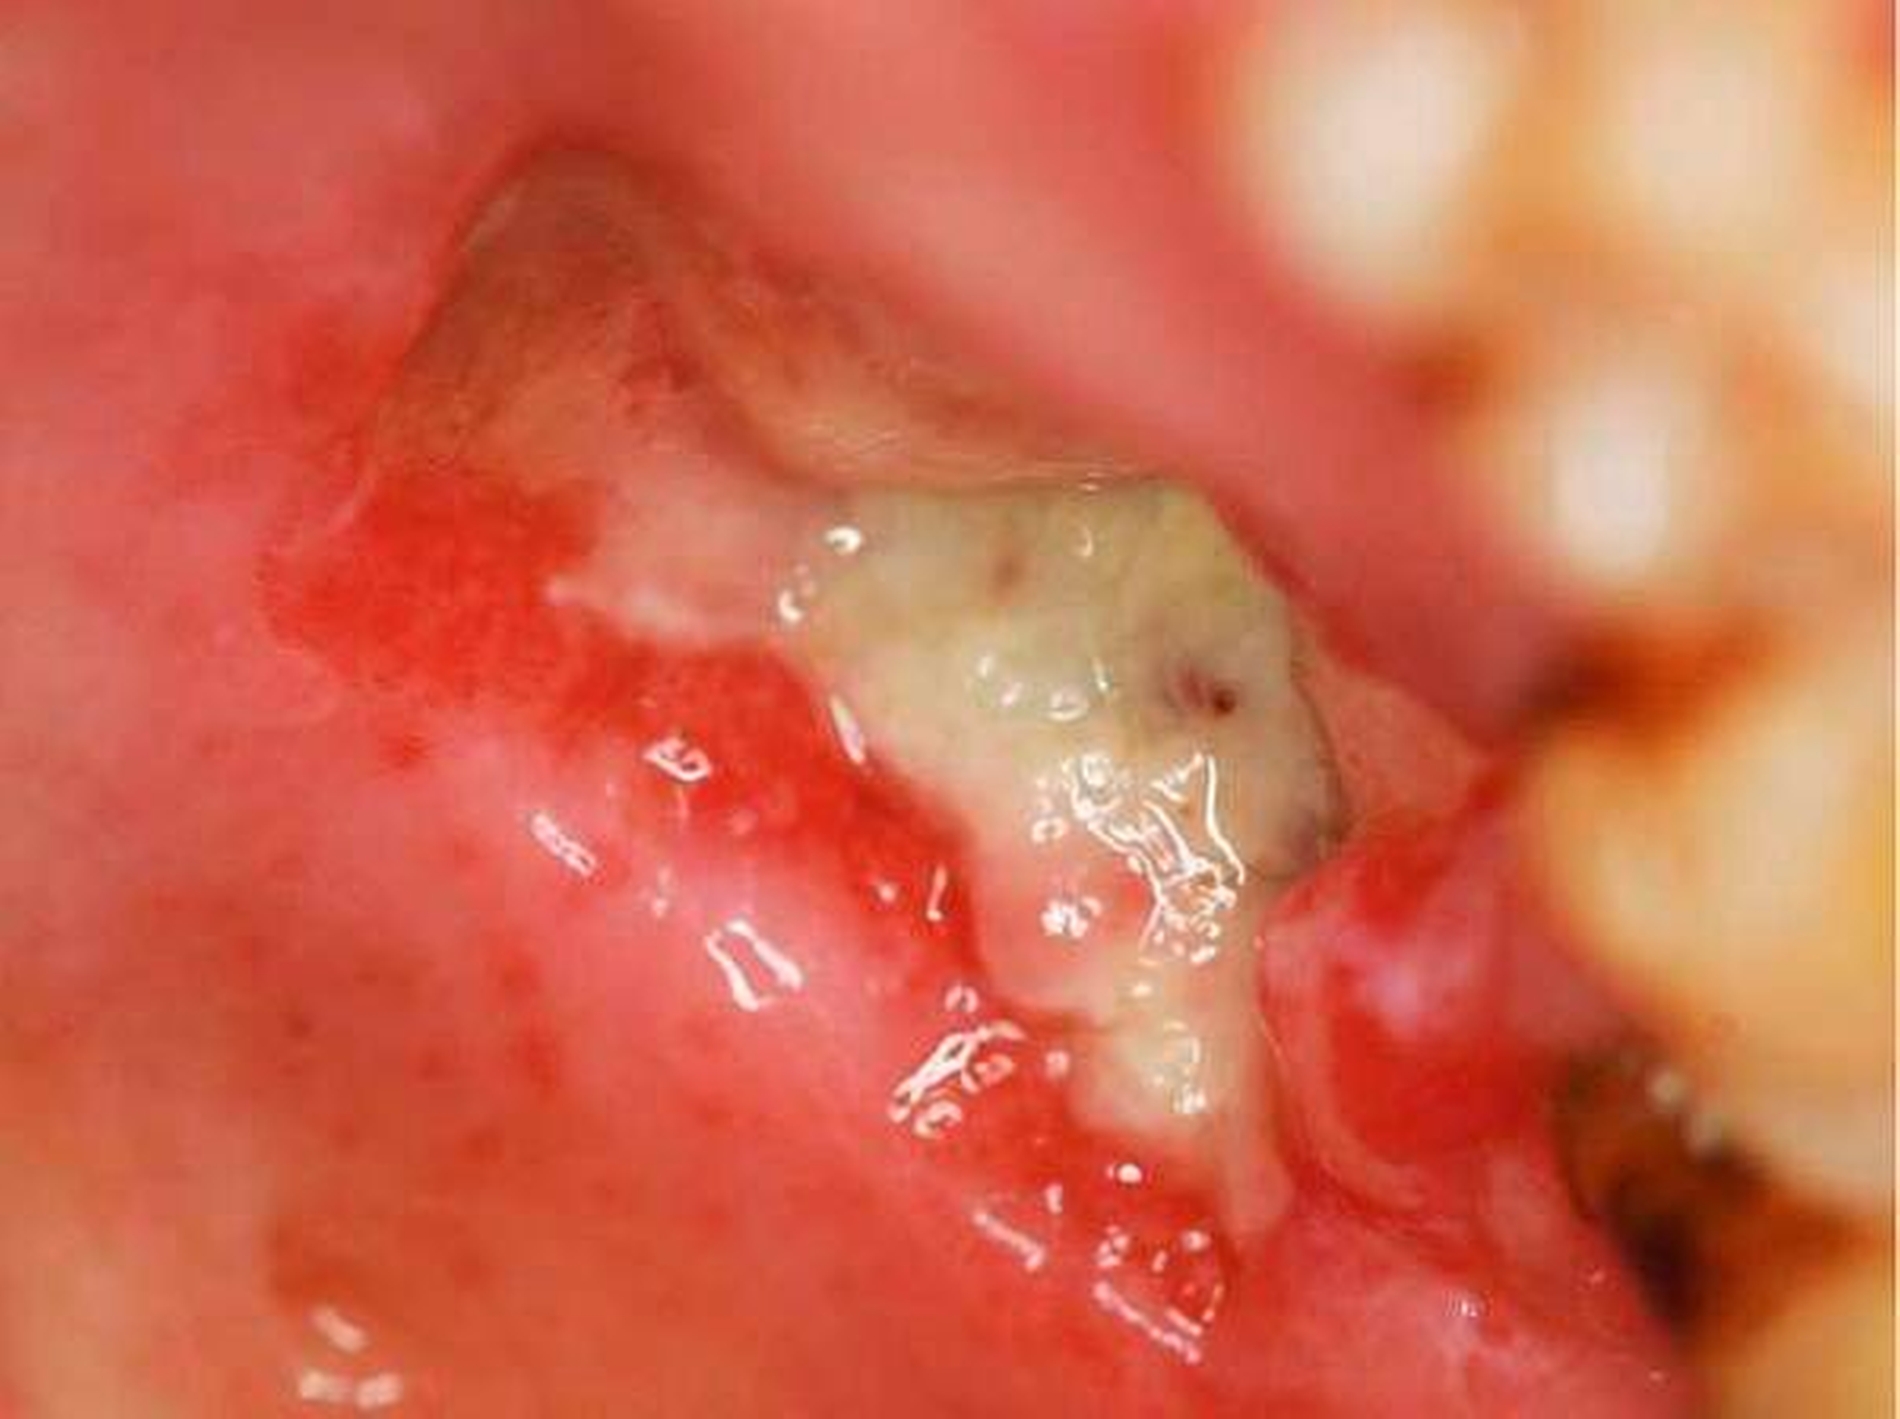

Bei der klinischen Untersuchung zeigte sich ein schmerzloser, 2 cm x 1,7 cm x 0,3 cm großer, polypös-prall-elastischer, nach regio 26 gestielter Lokalbefund (Abbildung 1 links).

Nach Auswertung des Bildmaterials und Vervollständigung der präoperativen Aufklärungen konnte die Exzision des Befunds problemlos unter ambulanten Bedingungen in Intubationsnarkose durchgeführt werden (Abbildung 1 rechts und Abbildung 3).

Die histopathologische Nachuntersuchung des Gewebeexzidats ergab den Befund eines echten polypösen Schleimhautfibroms ohne Anhalt für Malignität (Abbildungen 4a und 4b). Während der klinischen Nachsorge zeigte sich die per secundam ablaufende Wundheilung unter Zuhilfenahme einer Verbandsplatte und der täglichen Anwendung von 0,12-prozentiger Chlorhexidin-Mundspüllösung unter weiter bestehender immunsuppressiver Medikation und starkem Nikotinabusus zwar zeitverzögert, aber insgesamt unauffällig (Abbildung 5).